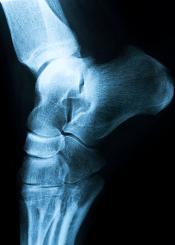

El diagnóstico se basará en la descripción del dolor que

haga el paciente. Con una simpleradiografíade perfil del pie se puede apreciar la presencia del

espolón calcáneo. Por lo general no se requiere realizar